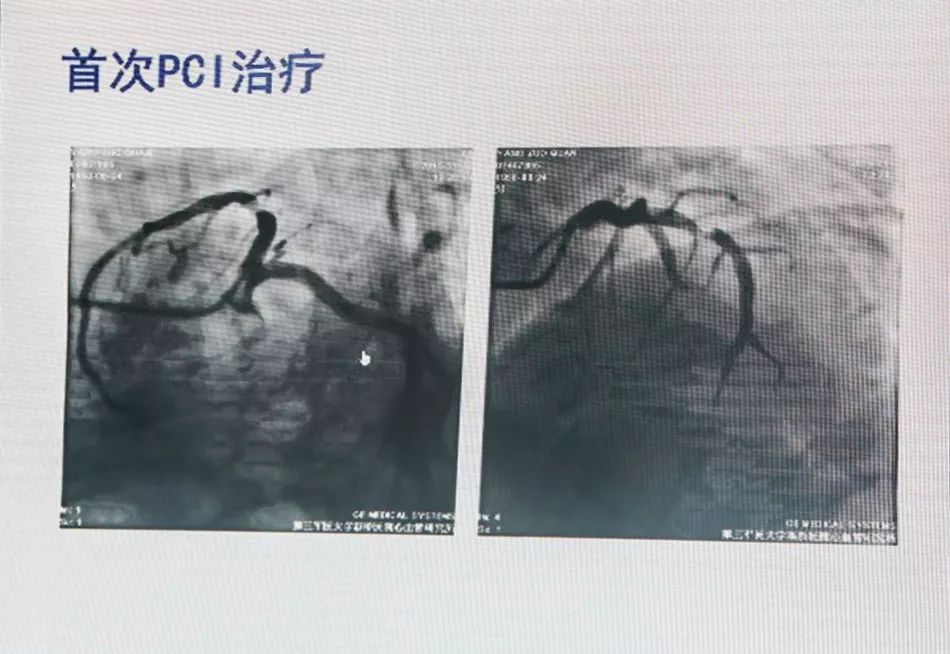

65岁,男性,以“劳力性胸闷胸痛3年,加重11天”入院。

既往糖尿病病史2年,未规律用药;脑梗死病史4年,现遗留步态不稳,未规律用药。

8日后再次胸痛

18:00患者外出就餐突发胸痛,持续不能缓解;

当地人民医院诊断考虑“急性心肌梗死”;

联系陆军军医大学第二附属医院胸痛中心,考虑亚急性支架内血栓形成,绕行急诊,PPCI。